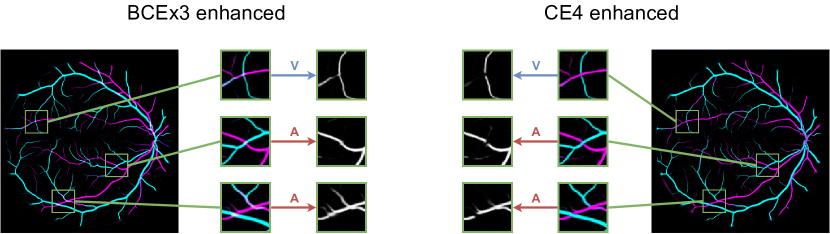

In Figure 8, the mean ROC and PR curves in RITE-test for the networks that were trained using the BCE3 and CE4 losses with and without image preprocessing (“enhanced” and “original”, respectively) are depicted.

Complementing the segmentation results, Figure 10 depicts the ROC and PR curves of the different approaches for the A/V classification in the RITE-test set. These curves are built considering only the pixels labelled as “vessel” in the ground truth, being “artery” the positive class.

Lastly, Figure 13 shows representative examples of the predicted probability maps that were obtained by the trained models using both losses and the enhanced retinographies as input. In each case, the figure depicts the RGB composition of the predicted maps for a better clarity.

In addition to the higher segmentation performance using BCE3, crossings are handled in a more intuitive way. In this case, crossing pixels are simply assigned to both artery and vein classes at a time and the network is able to detect them (see PR curve depicted in Figure 11) while allowing to achieve a continuous segmentation of both the arterial and venular trees. For CE4, differently, the crossings are mostly treated as a separate class (along with the uncertain vessels), either to detect them [39], or to let the network detect the artery or the vein above the other [36, 37, 40, 41]. There is also some approach in which the crossings belong to the same class as that of the upper vessel [38]. Nevertheless, whichever of these alternatives gives raise to incomplete segmentation maps for both arteries and veins. Multiple examples of this effect can be found in Figure 14. Taking all this into account, it can be stated that the MS strategy favors a better segmentation of the different structures, and handles the different cases in a much simpler way.